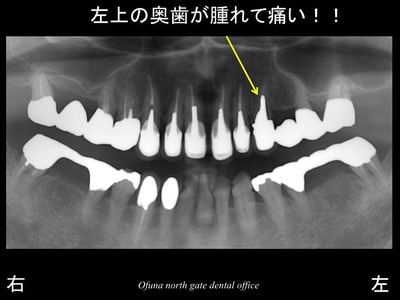

以下は初診時です。

上顎左側の奥から3番目の歯が

腫れて痛い!

とのことで来院されました。

診査の結果、歯根破折 していました。